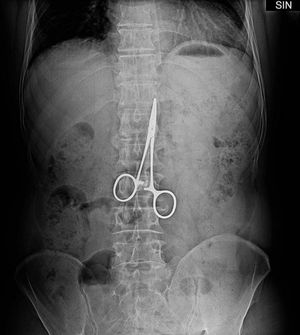

A man who went to hospital with stomach pain was found to have a surgical clamp inside his belly-from an operation 37 years before The Chinese man has gastric ulcer surgery in 1974 and had frequently suffered stomach pain in subsequent years His comments ' I thought it was my old stomach problem and each time I took stomach medication anti-inflammatory pills to relieve pain' with pain getting worst he went back to hospital and doctor discovered the 10cm long instrument before removing it in a 2 hour operation. According to doctor he was lucky because a part of abdominal wall had wrapped around the clamp from development of post surgical adhesions, prevent it from moving and potentially causing serious internal injury